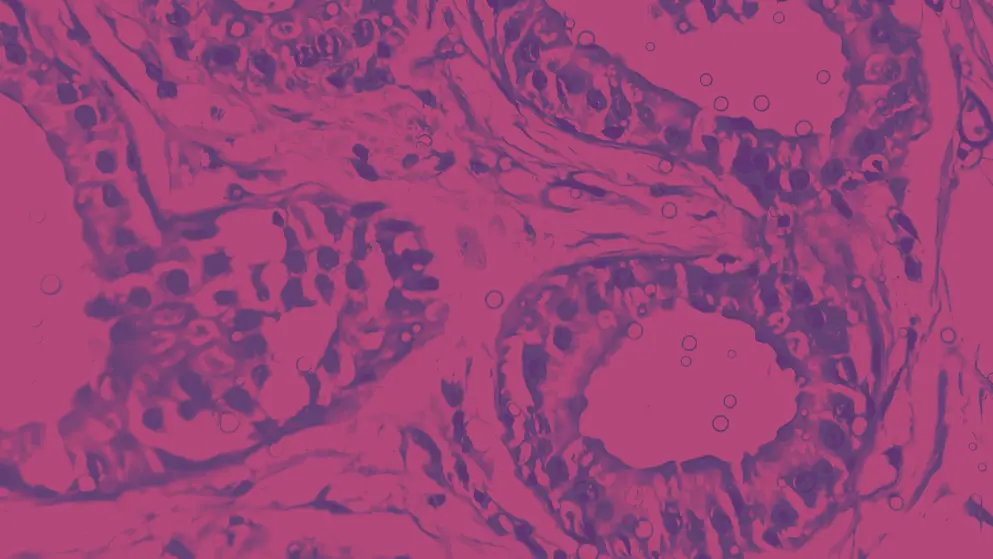

Hidradenitis Suppurativa Learning Zone